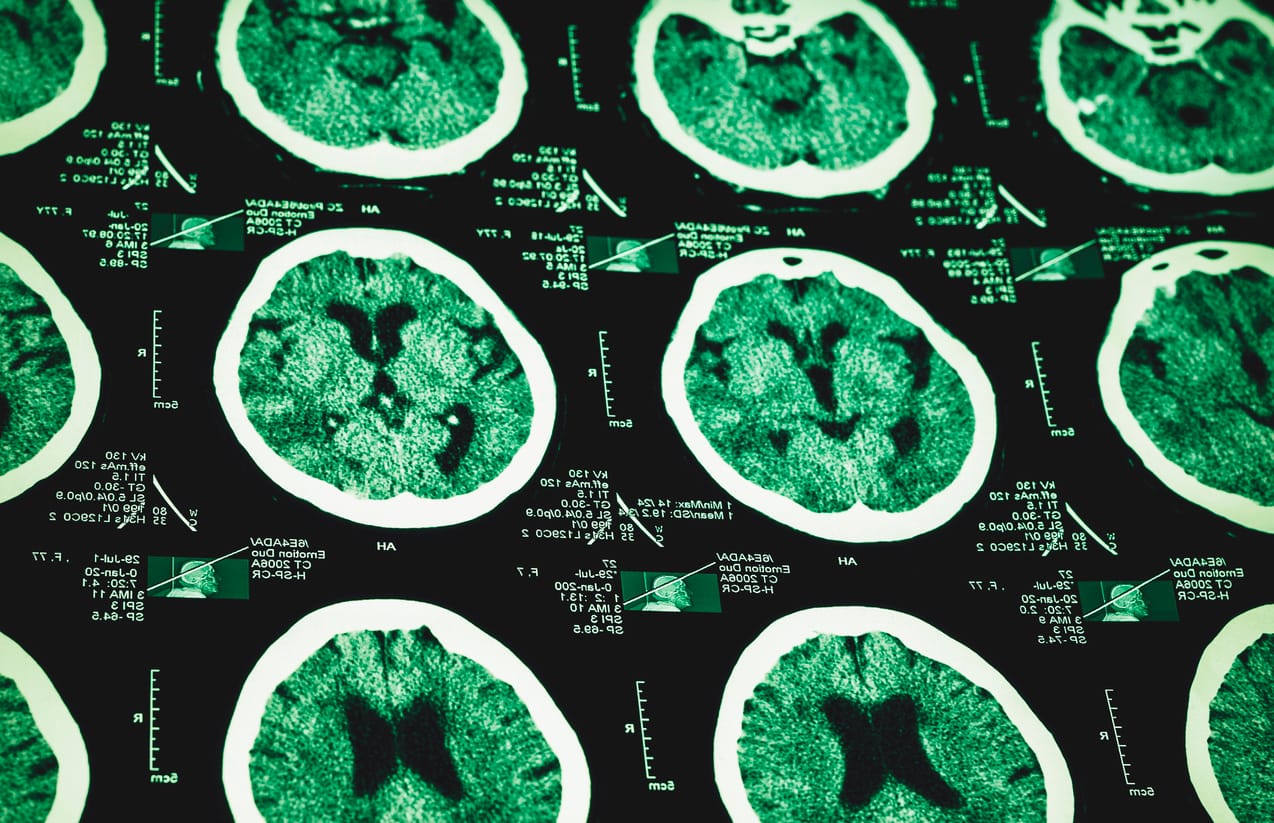

The issue in this case is acquired brain injury (ABI) rehabilitation. The paper spells out it is “expensive and (a) long-term endeavour” with “very little published information or debate” on which to build policy and delivery in Australia, especially within a context of “finite health budgets”.

“Slow-stream” in this context means the patients – with catastrophic brain injuries from accidents, falls or trauma – can stay well beyond the usual inpatient timeframes, allowing for slow gains, which is rare.